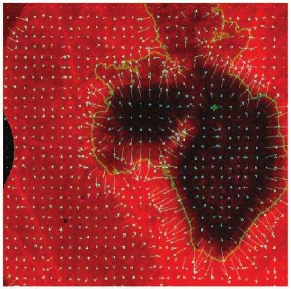

In this paper we propose a framework via a PDE-constrained optimization problem that can be solved with the splitting method, exploiting the fact that this procedure is easily parallelizable. We follow the PDE-based model by Gatenby [7] in a two-dimensional tissue. We estimate one of the model parameters (the destructive influence of H+ ions in the healthy tissue) using an inverse problem. It is possible to get data about the concentration of hydrogen ions [8] via fluorescence ratio imaging microscopy. In this approach, tumor invasion is modeled via a coupled nonlinear system of partial differential equations, which makes the numerical solution procedure quite challenging. These equations are solved using an Adaptive Finite Element Method (AFEM).

One of the experimental methods to obtain values of is by using fluorescence ratio imaging microscopy [8].